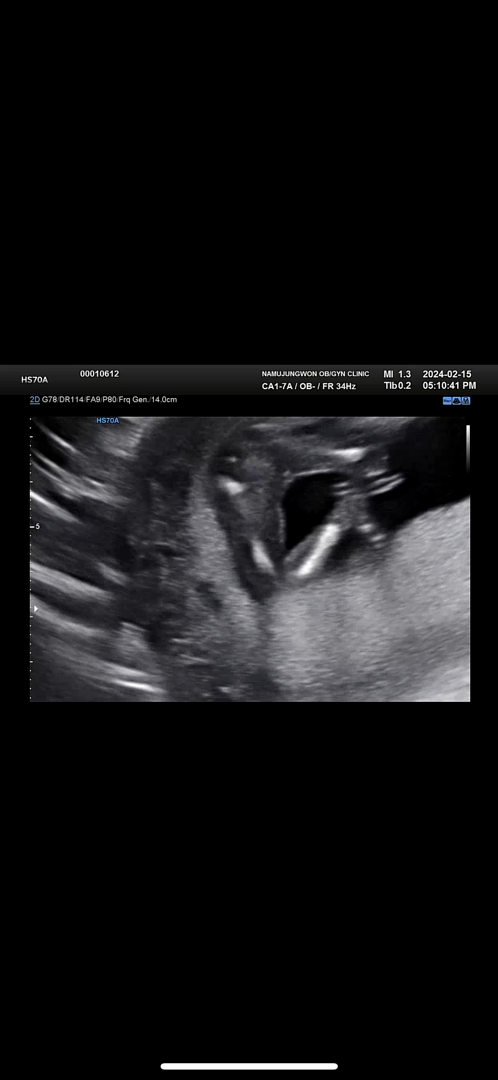

15주 딸맞는거 같은뎅 봐주세용

당담 원장님이 휴진이라 다른원장님이 봐주셨는데 다리 꼬고 있어서 안보인다고 다음에 올때 알려준다고 하는데 암만봐도 딸아닌가요